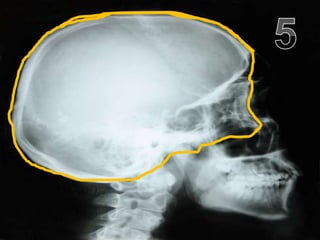

• Your brain is protected by the skull case

Copyright © 2010 Ryan P. Murphy

• Traumatic brain injury (TBI)

– A blow to the head that disrupts normal brain

function.

– A mild blow to the head can result in being

knocked unconscious.

• Repetitive collisions / concussions can

cause a number of serious brain

functioning problems later on in life.